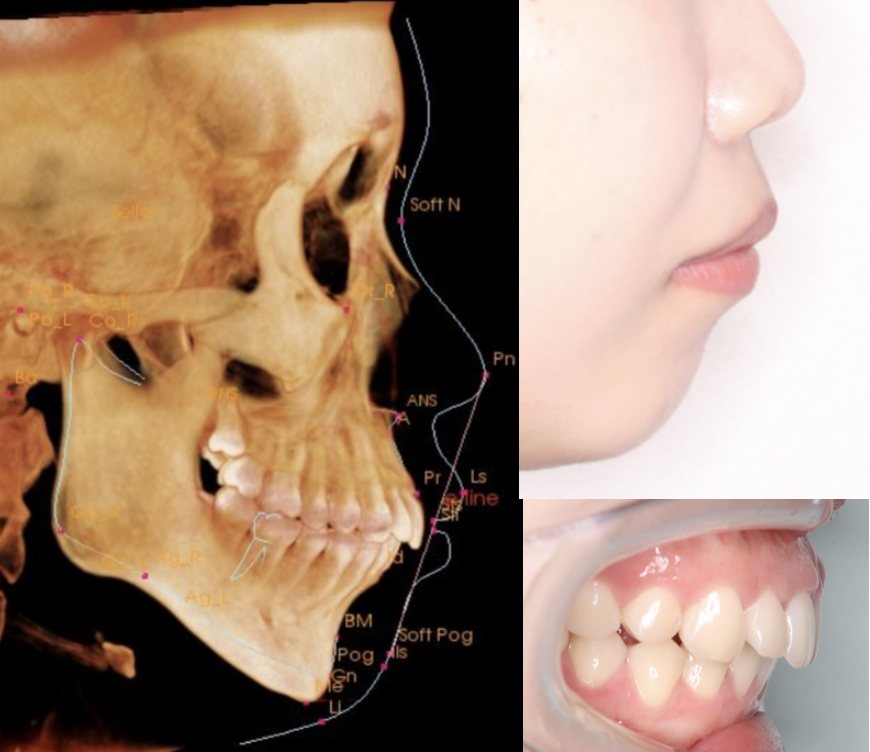

この2つを見極めるために、当院ではCTスキャンによる精密分析を初診時に行っています。

骨格的な出っ歯・口ゴボのイメージ

ℹ️ 外科矯正の適応は、CTスキャンとセファロ分析による骨格の精密評価が必要です。「手術が必要かどうか」は、見た目だけでは判断できません。当院では初診時のCT分析でご説明しています。

この骨格の分析に使うのがセファロ(頭部X線規格写真)分析です。詳しくは以下の記事をご覧ください。

「矯正だけで治るか」「外科矯正が必要か」——この判断は、見た目だけでは絶対にできません。当院ではミリ単位で顎の骨の位置を特定し、将来の横顔のシミュレーションを行うため、CTスキャンを使った骨格の3D分析を初診時に行っています。